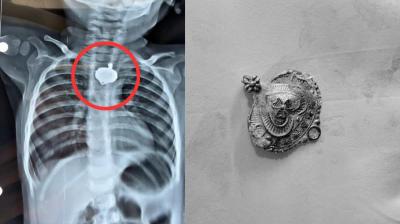

बच्चे की नजर का ऐसे लगाएं पता, डॉक्टर के पास जाने से पहले

मम्प्स-मीजल्स के बाद नई बीमारी का खतरा, बच्चों पर मंडरा रहा संकट